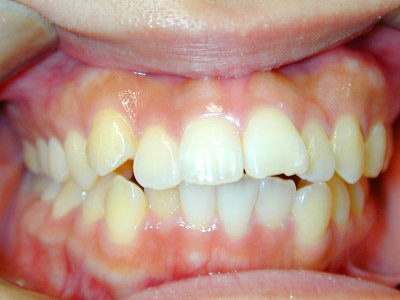

部分矯正ですが上下顎中切歯の正中も治療前に比べて大きく改善しています。

歯列矯正の副作用として治療中のむし歯の発生や歯周病の悪化の危険性以外にも、

歯根吸収、歯根破折、歯髄変性、歯髄壊死などの可能性があり、注意が必要です。

ストリッピングを行なっているのでエナメル質の範囲で隣り合った歯と歯の間の歯質を切削しています。

治療期間:1年2ヶ月

治療費用:43万円